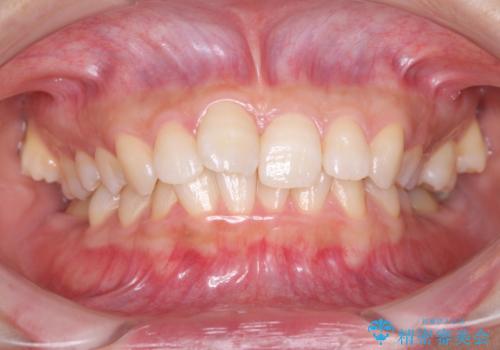

インビザライン 前歯のがたつきを目立たず矯正

口が少し閉じにくい インビザラインによる非抜歯矯正

出っ歯 すれ違い咬合の改善

奥歯の倒れた歯を改善 インビザラインでの矯正治療

気になる前歯を整えたい インビザライン・ライトでの矯正治療